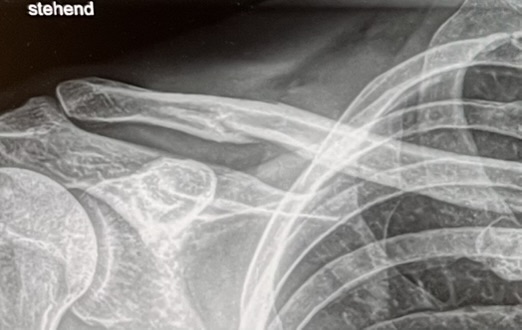

Vorgestern auf Sizilien einen Schlüsselbeinbruch zugezogen. Mal sehen was der deutsche Arzt Montag dazu sagt. Ich finde ja dass man es kaum sieht. Das schmerzhaften Knacken bei jeder Bewegung ist aber eindeutig. Mit dem italienischen Radiologen im Provinzkrankenhaus war die Verständigung schwer.

Mich würde interessieren ob es hier auch Erfahrungen mit solchen scheinbar gut positionierten Brüchen gibt? Die Berichte die man liest sehen immer wesentlich komplizierter aus.

Am 21.01.2025 nach zwei Wochen nochmal eine Röntgenaufnahme. Bruch hat sich leicht verschoben, ist aber noch sehr gut platziert für eine konservative Therapie. Zur Verschiebung muss man wissen, dass ich nach dem ersten Röntgen noch das Fahrrad mit Gepäck über meherer Bahnhoftreppen tragen musste. Und dann den 30 Kg Fahrradkoffer von Sizilien alleine nach Hause bringen ist auch nicht ganz ohne Belastung machbar ;-)

Nach 6 Wochen sieht man auch den Kallus leicht als halkreisförmigen Schatten unter dem Bruch.